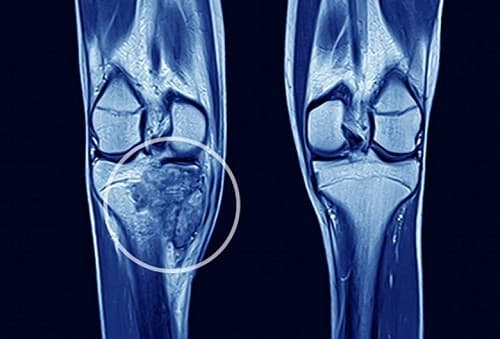

Ung thư xương là bệnh lý ác tính bắt nguồn ở xương, chủ yếu là xương dài như cánh tay, chân do sự phát triển bất thường của các tế bào trong xương.

Ung thư xương thường phổ biến ở lứa tuổi thiếu niên và những người trẻ tuổi nên thông thường, nó thường bị nhầm lẫn với các dấu hiệu phát triển xương khi dậy thì. Triệu chứng hay gặp ở bệnh nhân ung thư xương là đau xương, đau kéo dài ở khu vực khối u, sưng, giảm khả năng vận động, gãy xương, mệt mỏi, sốt cao hoặc ra mồ hôi, giảm cân.